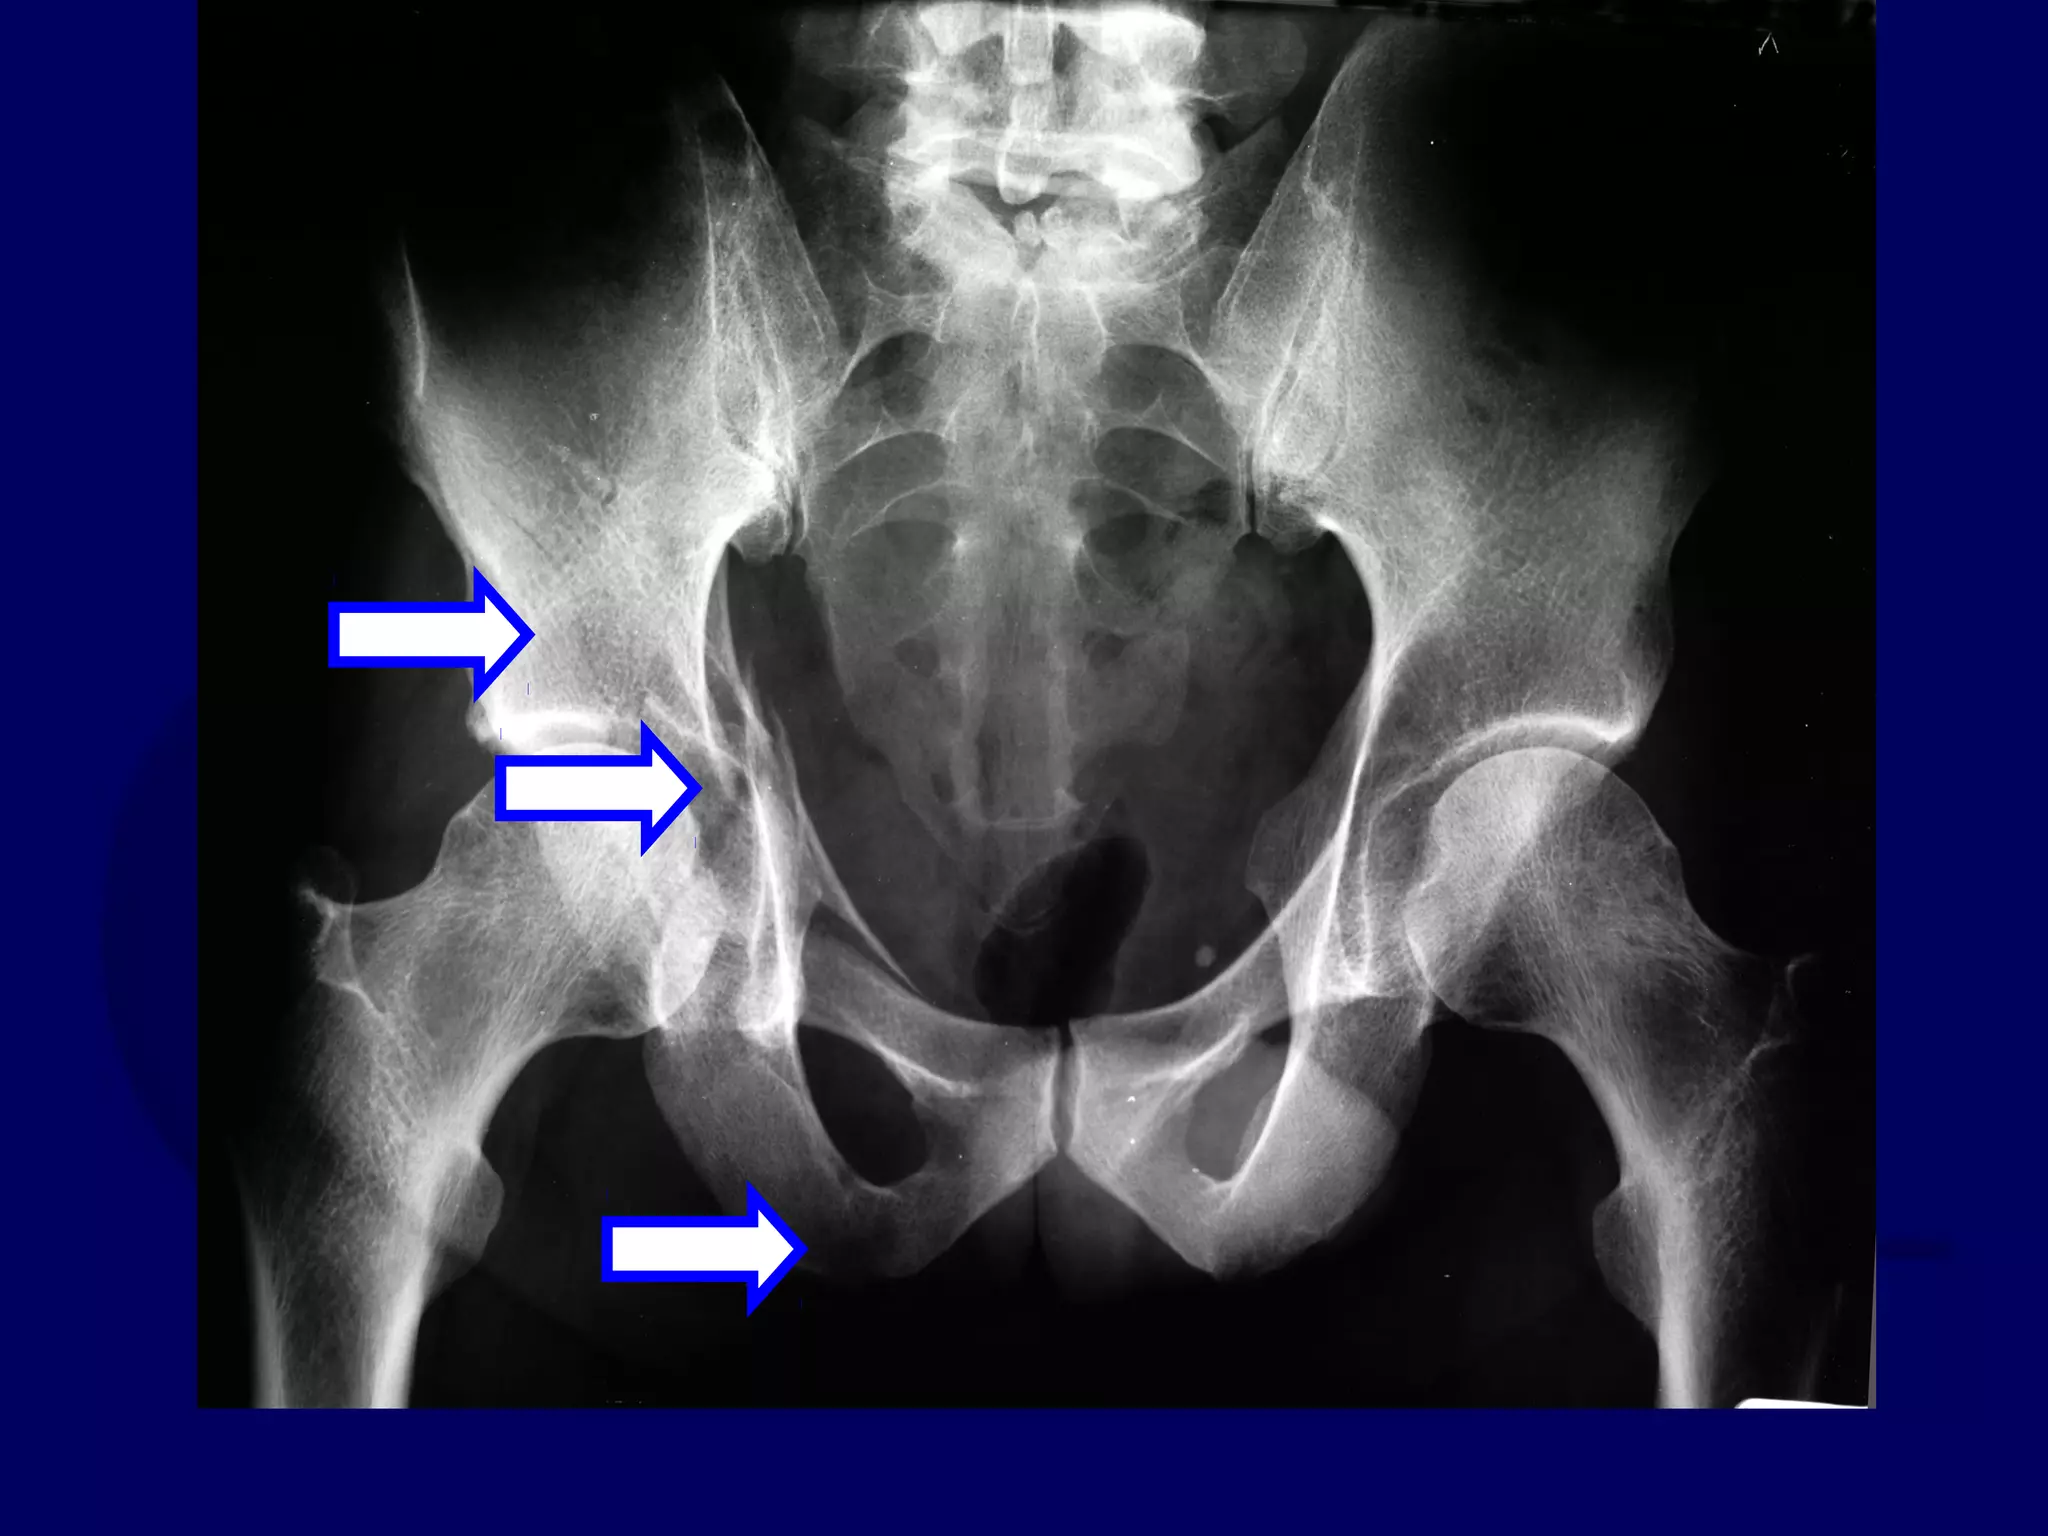

Ilioinguinal Approach

Anterior Column Fx

Isolated Injury

73 Y.O. Male

J.W. 00.10.14